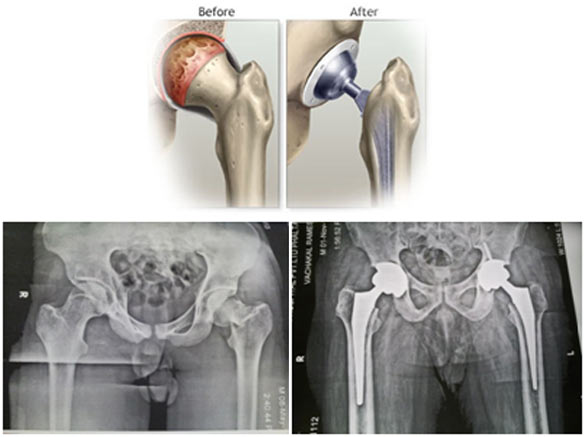

Hip Replacement

Hip replacement surgery replaces a damaged hip joint with a prosthetic implant to relieve arthritis pain and restore movement.

A total hip replacement involves replacing both the acetabulum (hip socket) and the femoral head, while hemiarthroplasty replaces only the femoral head.